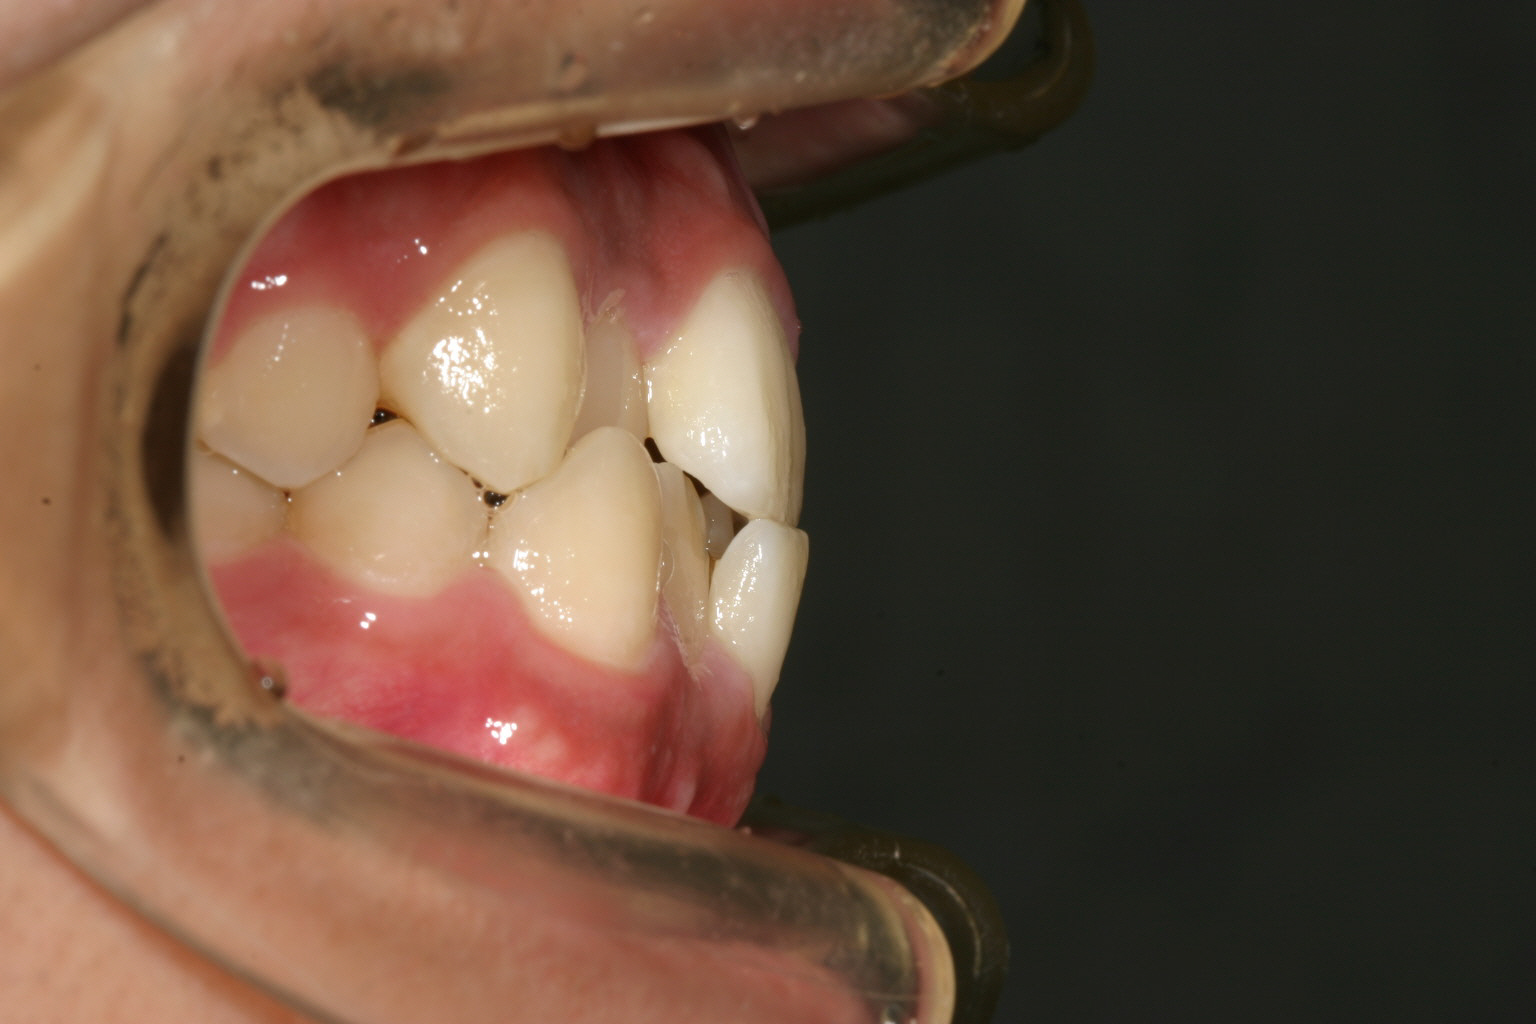

歯列弓が狭い為に前歯が並ばずガタガタしています。

下顎もアーチが狭い為叢生になっています。

横から見ると少ししゃくれ気味です。